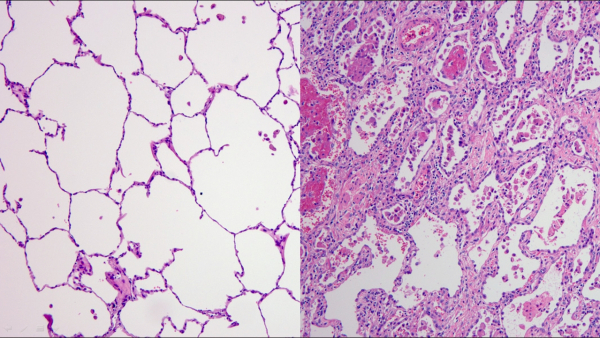

그렇지만 환자는 바이러스만 사라졌을 뿐 폐 상태가 나빠졌다. 흉부X-ray 검사 결과에서는 심한 특이사항이 발견되지 않았지만, 흉부CT 검사 결과 양측 폐에 광범위한 침윤소견과 폐섬유화 속도가 상당히 빨랐다.

에크모센터장 흉부외과 김형수 교수는 "코로나19 환자 중 국내에서 최고의 중증치료 사례였으며 코로나바이러스에 감염된 폐를 떼어낼 때 건강한 폐와 다르게 크기도 작게 수축 됐고 마치 돌덩이처럼 폐가 딱딱한 느낌이었다"며 "건강하고 젊은 코로나19 감염증 환자도 폐섬유화 진행 속도가 빨라 폐이식까지 갈 수 있으니 젊다고 방심하지 말고 감염을 막기 위한 사회적 거리두기, 마스크 착용 등의 노력을 지속해야 한다"고 강조했다.